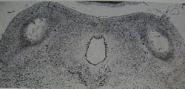

Figure

7 is from the article by William F. Windle that

appeared in the October 1969 issue of the Scientific

American, and shows the damage that can be caused

by a brief period of asphyxia at birth.  The moment I

looked at these pictures I gasped; this certainly

seemed to me the reason Conrad, my five-year-old

son who had been resuscitated at birth, was not

learning to speak.

Damage (top) found in

the inferior colliculi in monkeys

subjected to sudden, catastrophic

asphyxia - inflicted by delivering

the head of infant monkeys into a

saline-filled sac, and clamping the

umbilical cord.  Compare with the

appearance of the inferior colliculi

in a monkey born normally

(bottom).

These pictures were published in

the Scientific American in October

1969 as part of an article by

William Windle on asphyxia at

birth. They were also published in

the article by

Faro & Windle (1969).

Figure 7: